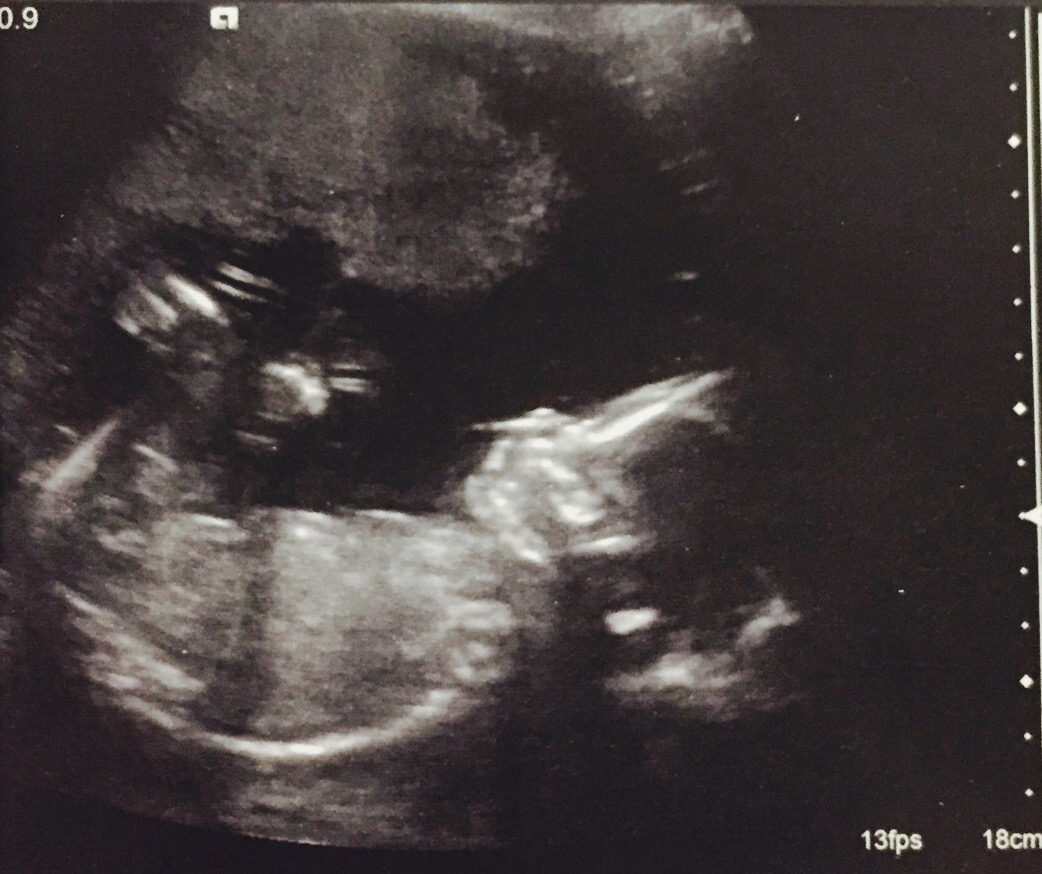

20+5 week scansAttachment 35790Attachment 35791Attachment 35792